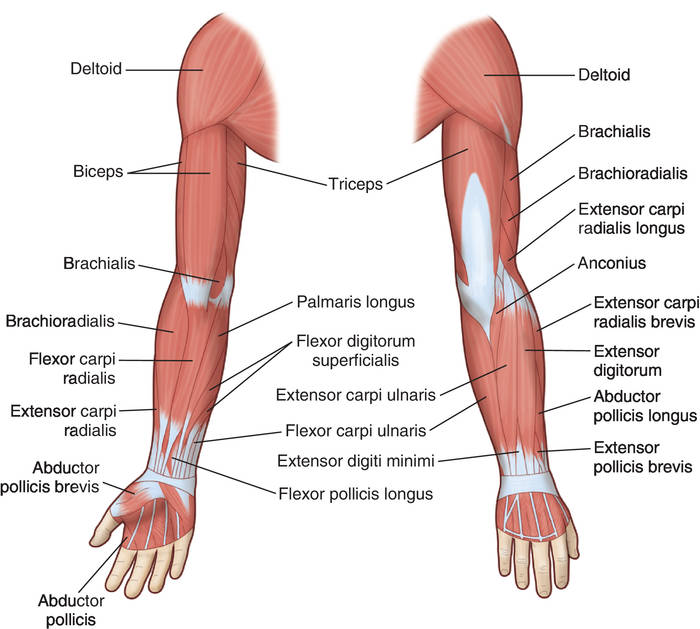

Анатомия и функции мышцы brachioradialis